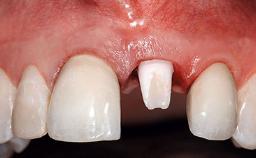

A 36-year-old male patient with a compromised maxillary central incisor was referred by his general dentist for consultation. The patient’s chief complaints were the gradual debonding of a temporary crown on the right central incisor and unsatisfactory esthetics due to an increasing diastema between the right central and lateral incisors. The patient reported a traumatic event some years previously, when a crown had been placed after root-canal treatment. The referring dentist wanted to provide a new crown restoration, but was concerned about the condition of the residual root. Anamnesis was negative for any other dental or periodontal pathology in the remaining dentition. The patient reported taking no medications: He was a smoker (10 to 15 cigs/day) and had realistic esthetic expectations.

Prosthesis Type FDP